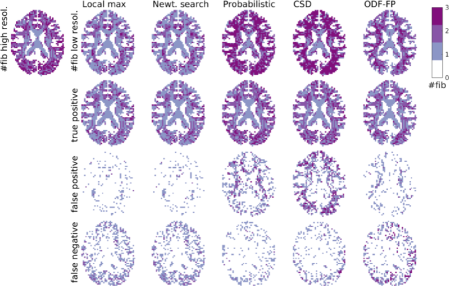

Refer to caption

Figure 7: Fiber directions identified in a subsection of a transversal slice in both high and low resolution versions of a HCP dataset. In the low resolution datasets, the fibers are identified by 5 algorithms: local maximum search (DSIStudio), Newton search (MRtrix3), probabilistic estimation (FSL, bedpostx), constrained spherical deconvolution (MRtrix3, dwi2fod msmt_csd, and ODF-Fingerprinting (ODF-FP). The arrows indicate one of the voxels where ODF-FP identified fiber directions which are missed by some of the other algorithms.

Figure 8: Maps of the number of fibers identified in the high and low resolution versions of a HCP dataset (top row). The low resolution dataset was processed with 5 algorithms (local maximum search (DSIStudio), Newton search (MRtrix3), probabilistic estimation (FSL, bedpostx), constrained spherical deconvolution (MRtrix3, dwi2fod msmt_csd, and ODF-Fingerprinting (ODF-FP) and the number of correctly identified (true positive, second row), wrongly identified (false positive, third row) and missed (false negative, bottom row) fibers were calculated relative to the reference high resolution dataset. ODF-FP shows a larger number of true positive fibers at the cost of a somewhat higher number of false positive fibers.

Evaluation of in vivo fiber direction identification can be performed by comparing fiber directions found in down sampled DWI with those present in high resolution DWI. The latter thus form an internal reference which is otherwise absent in in vivo data. Fig. 7 illustrates the setup of such an experiment; the directions found in a LR voxel (yellow arrows) are compared to those found in the corresponding HR voxels (yellow square in the panel on the right). In the indicated voxel, ODF-FP, CSD and the probabilistic method successfully identify the second fiber bundle. However, the probabilistic method and CSD also identify a number of false positive fibers. Maps of the number of correctly (true positive) and wrongly (false positive) identified fibers (Fig. 8, second and third row) confirm these findings over the whole volume.